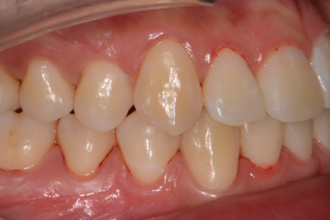

치아교정

굿프렌즈 치과 임상 케이스